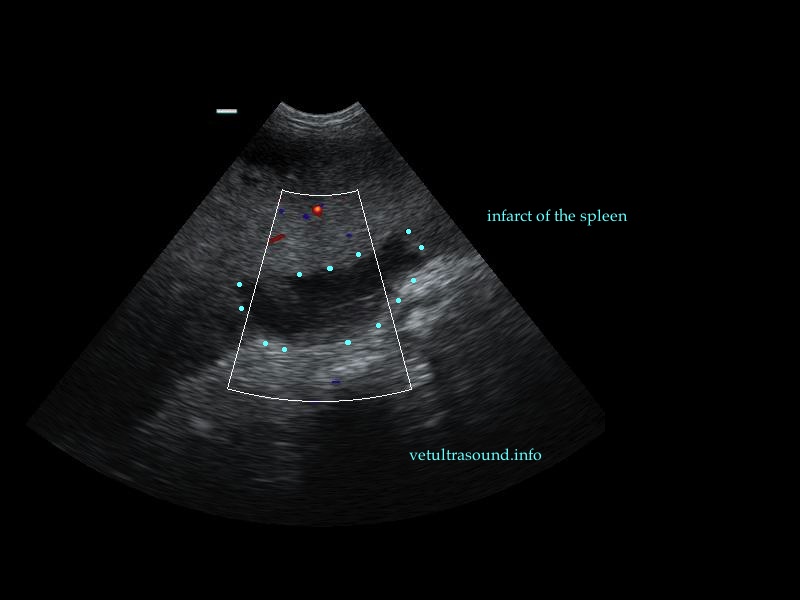

Ευρήματα: Η κεφαλή του σπλήνα βρέθηκε μετατοπισμένη ( στραμένη προς τα οπίσθια άκρα) με υποκαψικές περιοχές υποηχογένειας, χωρίς αιμάτωση (pic 1,2,3). Το τμήμα αυτό του σπλήνα ήταν διογκωμένο σε σχέση με το υπόλοιπο όργανο και το μεσεντέριο λίπος που το περιέβαλε ήταν έντονα υπερηχογενές. Στο συγκεκριμένο σημείο του σπλήνα τα μεγάλα αγγεία δεν είχαν ροή αίματος κατά τον έλεγχο με έγχρωμο Doppler (pic3). Αντίθετα το σώμα και η ουρά του οργάνου είχαν φυσιολογική αιμάτωση και μέγεθος (pic 4,5).

Διάγνωση: Η εικόνα αυτή θα μπορούσε να οφείλεται σε εμφράκτα τα οποία δημιουργήθηκαν είτε από θρόμβους ή σηπτικά έμβολα, είτε από μείωση της αιματικής ροής της περιοχής. Εξαιτίας της αλλαγής της θέσης του σπλήνα, του υπερηχογενούς μεσεντέριου λίπους που περιέβαλε την κεφαλή του οργάνου και των εμφράκτων στο παρέγχυμά του, η διάγνωση που τέθηκε είναι η μερική συστροφή του σπλήνα ή η παροδική διακοπή της αιμάτωσής του. Αυτό θα μπορούσε να έχει προέλθει από διάταση ή μερική στροφή του στομάχου, λαμβάνοντας υπόψιν το ιστορικό και τη φυλή του σκύλου. Η αιματουρία προήλθε πιθανά λόγω αιμόλυσης, εξαιτίας της συμφόρησης του σπλήνα. Έγινε σπληνεκτομή όπου και επιβεβαιώθηκε η μερική στροφή του οργάνου με αποτέλεσμα τον στραγγαλισμό μεγάλου μέρους των αγγείων του.